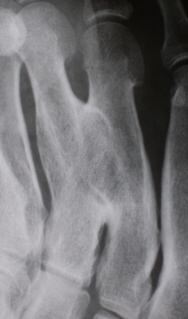

Иллюстрация 1. Рентгенограмма в прямой стандартной проекции. Определяется патологический синостоз между 3 и 4 плюсневыми костями. Определяется некоторое утолщение и деформация проксимальной ½ 2 плюсневой кости.